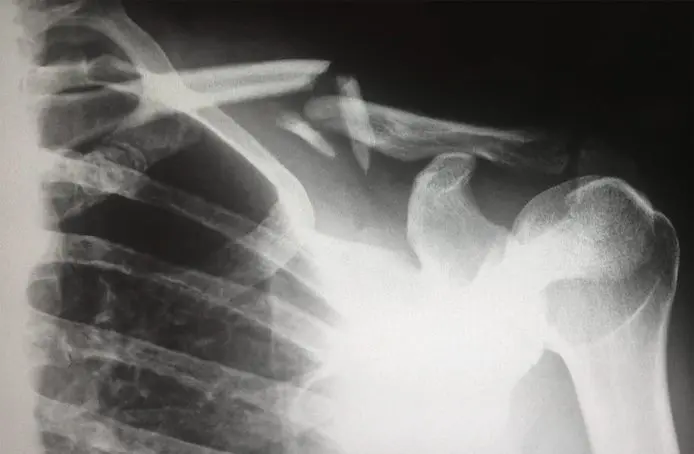

This one is sometimes hard to miss, as it’s sometimes inevitable. This can happen to anyone and anywhere, due to spills or any kind of residue on the floor causing people to slip. Trips could also happen quite regularly, as the workspace might not be as organized, so tripping on random bricks or things on the ground is not off-limits. This might result in broken bones, head and spine injuries, and a lot more. But be smart if some of these things happen, as falls can easily be faked, but that’s what surveillance comes in to save you, hopefully your fall is recorded and used as evidence to support your case!

This type of injury is a bit tricky, as a lot of things might happen, depending on the job and the equipment you are working with. Different reasons might also cause these types of injuries like unsafe products, flimsy equipment, or unsafe workspace in general. This is more common for construction workers or anyone in the manufacturing or construction field that works with heavy equipment and dangerous objects. Depending on the severity and the reason behind the accident, you’ll get the right compensation for your injury!